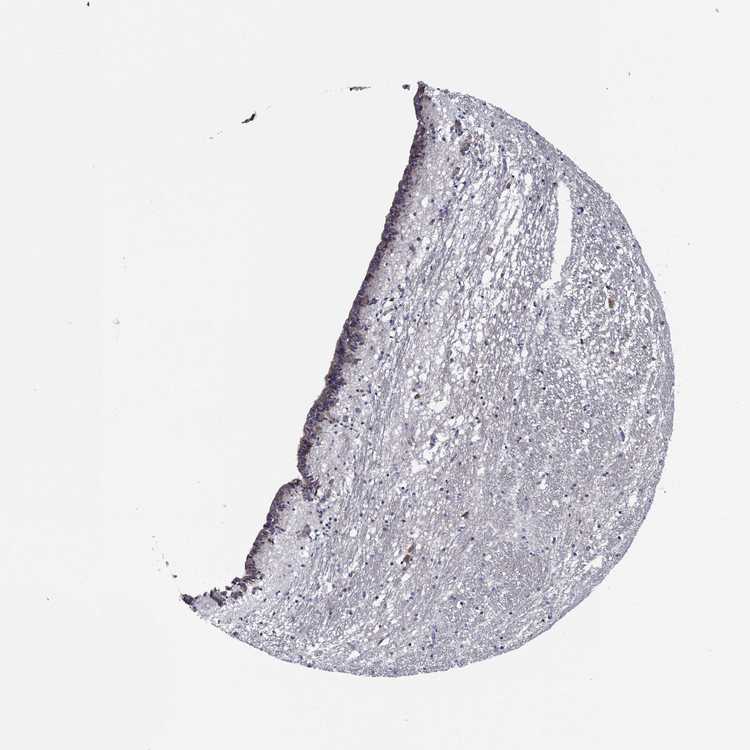

CAUDATE - Antibody stainingi

Antibody staining in the annotated cell types in the current human tissue is reported as not detected, low, medium, or high, based on conventional immunohistochemistry profiling in selected tissues. This score is based on the combination of the staining intensity and fraction of stained cells.

Each image is clickable and will lead to virtual microscopy that enables deeper exploration of all samples and also displays staining intensity scores, fraction scores and subcellular localization as well as patient and tissue information for each sample.

Antibody HPA036159Antibody HPA057384

Glial cells LowNot detected

Neuronal cells MediumHigh